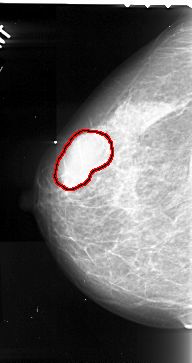

A_1061_1.RIGHT_CC

FILE: A_1061_1.RIGHT_CC.OVERLAY

TOTAL_ABNORMALITIES 1

ABNORMALITY 1

LESION_TYPE MASS SHAPE LOBULATED MARGINS CIRCUMSCRIBED

ASSESSMENT 3

SUBTLETY 5

PATHOLOGY MALIGNANT

TOTAL_OUTLINES 1

BOUNDARY